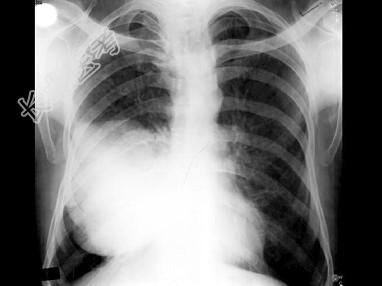

- 单项选择题50岁,男, 右侧胸痛、咳嗽、咯血3月,结合图像, 最可能的诊断是 ( )